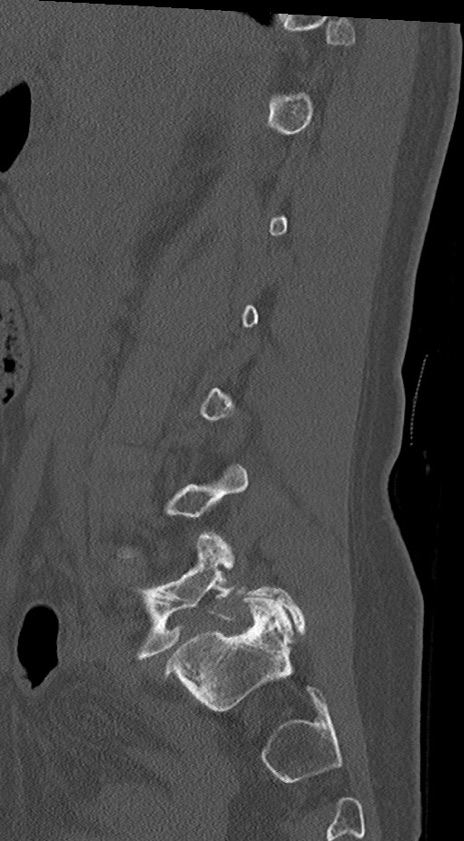

腰椎CT

冠状断像